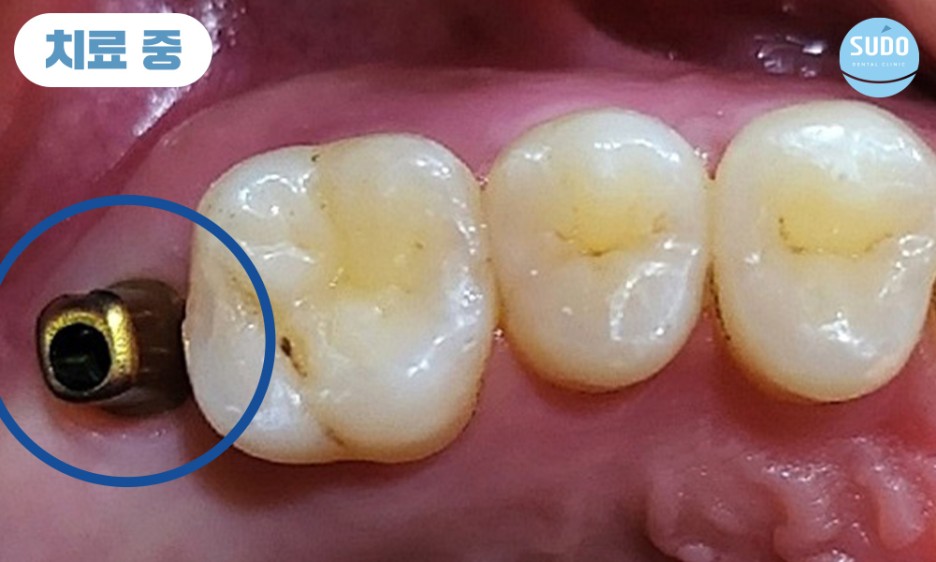

식립 당일 힐링 어버트먼트를 결합한 채로 본래의 잇몸뼈와 안정적으로 융합될 수 있도록 충분한 기간 동안 기다려주었습니다.

힐링 어버트먼트란, 임플란트를 보호하고 잇몸 조직의 적절한 치료를 촉진하며 미관을 개선하고 최종 보철물의 배치를 위한 안정적인 기준을 제공하기 위한 목적으로 사용합니다.

잇몸뼈의 융합을 위해 약 2개월 정도 기다린 후 영도임플란트치과 본원에서는 맞춤형 지대주 및 보철을 완성해 드렸습니다. 맞춤형 지대주를 사용할 경우 기성품으로 제작된 똑같은 크기와 모양의 지대주가 아닌 환자분들 개개인의 구강구조에 맞추어 제작한 것이므로 잇몸 라인에 맞춘 제작으로 틈이 생기지 않고 음식물 찌꺼기의 끼임을 방지해 주어 염증을 예방하는 효과가 있습니다.